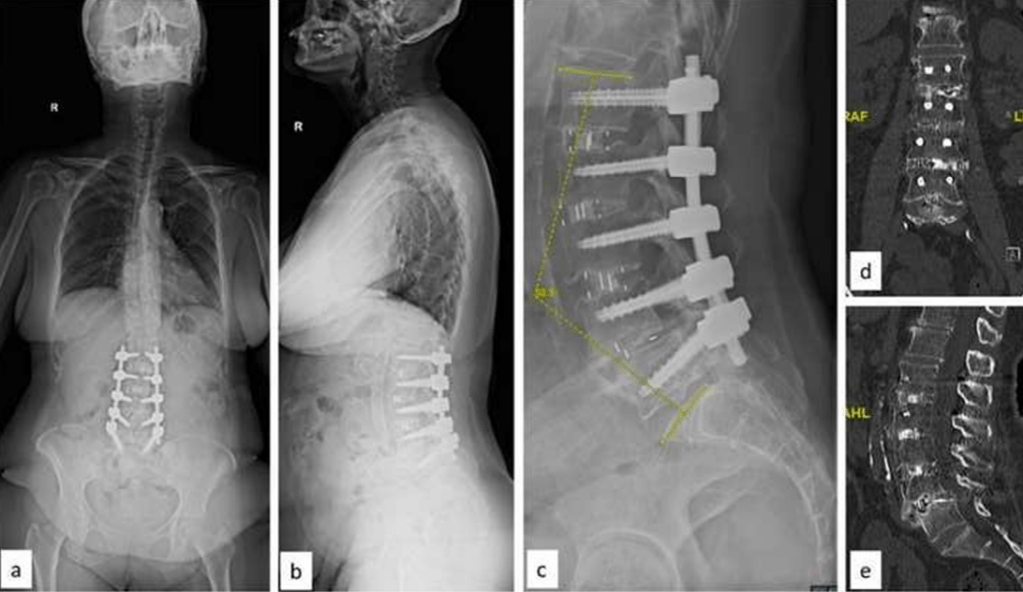

A Staged-OLIF Approach Can Minimize Construct

Lengths In Adult Spinal Deformity – A Case Series and Literature Review